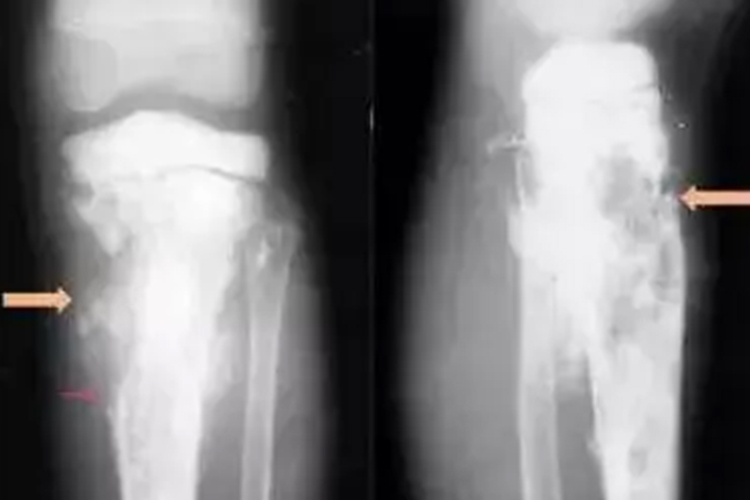

骨肉瘤X线的表现包括骨质破坏、肿瘤骨、软组织肿块等。骨质破坏表现为骨松质呈小斑片状骨破坏,皮质边缘可见小而密集的虫蚀样破坏区,在皮质内表现为哈弗斯管扩张而呈筛孔状破坏。以后骨破坏区融合扩大形成大片的骨缺损。肿瘤骨表现为瘤骨的形态主要有云絮状、斑块状、针状。软组织肿块则提示肿瘤已侵犯骨外软组织,肿块多呈圆形或半圆形,境界多不清楚。